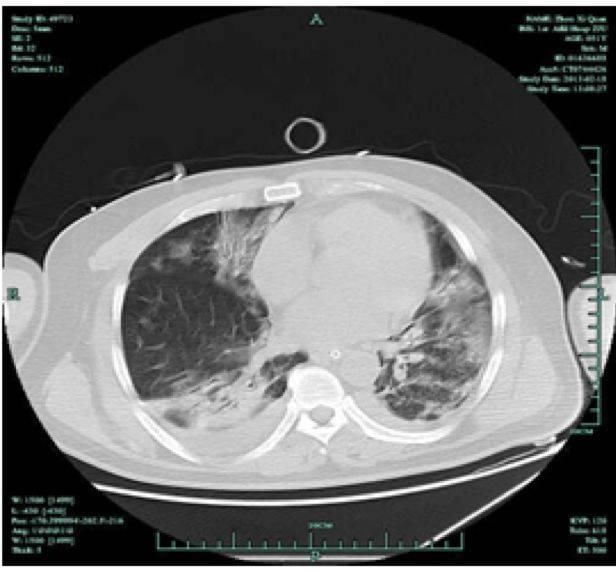

•化疗后发热,咳嗽,气急,氧合下降考虑肺炎入ICU气管插管。机械通气10天后。

•机械通气维持,氧浓度80%,点头样呼吸40次/分,SPO2 82%体温最高40°,当日尿量800ml

•治疗方案:舒普深+万古霉素+卡泊芬净更换为泰能+万古霉素+伏立康唑。甲强龙40mg BID 1周,考虑到免疫功能低下,停药3天。

•痰培养:鲍曼不动杆菌

•化验检查:WBC 21000/dl,N92%,HB9.2g/dl,PL 84000/dl,CRP 185,PCT 8.5,Cr 75,白蛋白2.8g/dl,PT14s,D-二聚体5600